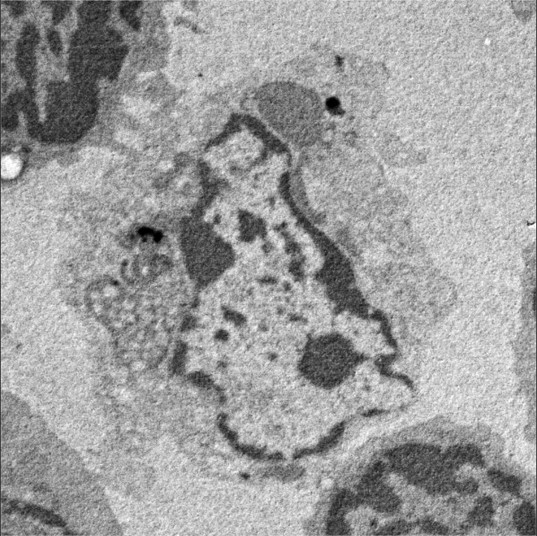

图片来源:神户大学医学研究生院结构医学·解剖学部/新田亮教授

研究结果清楚地表明,树突状细胞能杀死缺乏CD47的T细胞。这不仅首次揭示了存在CD47缺陷T细胞消失的机制,还揭示了树突状细胞完全意想不到的能力。